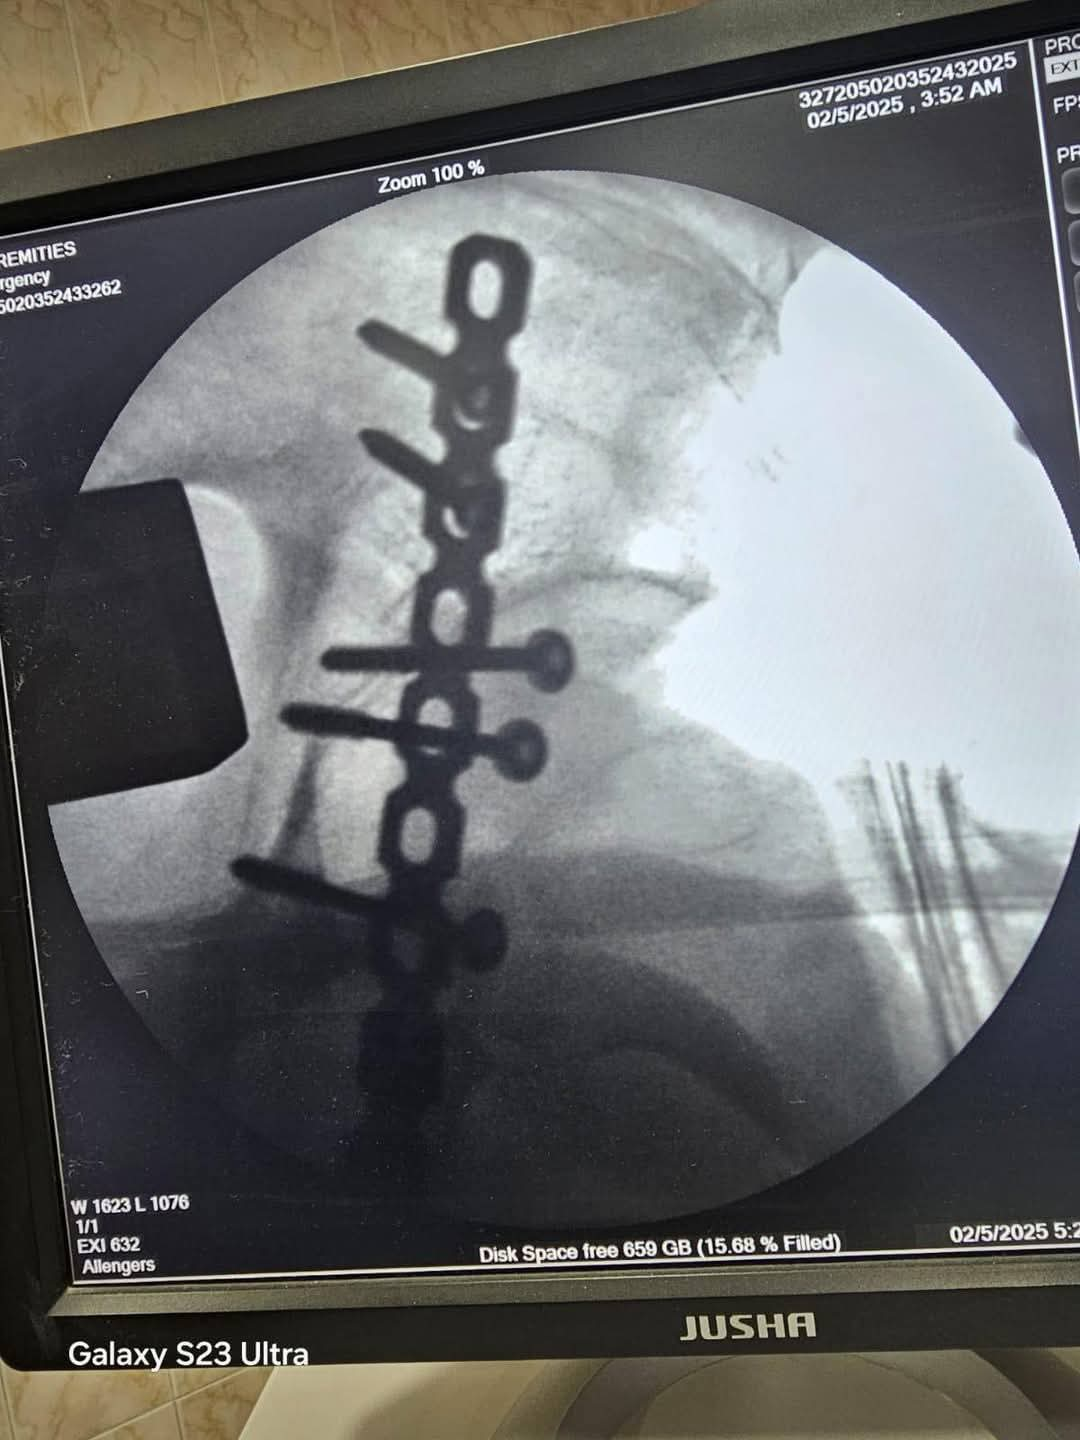

بعد استقرار الحالة، تم تجهيز المريض لإجراء الجراحة العاجلة التي استغرقت قرابة ساعتين ونصف، ونجح خلالها الفريق الطبي في تثبيت الكسور باستخدام شرائح ومسامير، والتأكد من عودة المفصل إلى وضعه الطبيعي.

أُجريت الجراحة تحت إشراف الأستاذ الدكتور الشربيني علي، استشاري ومدرس جراحة العظام، وبمشاركة الدكتور أحمد النعماني، والدكتور أحمد نصار، والدكتور أحمد جمال، وبمساندة فريق التخدير بقيادة الدكتور محمد جمال البلشي، والدكتورة ولاء محمد، إلى جانب أطقم التمريض والتخدير والأشعة والصيدلة.

جاء ذلك بإشراف الدكتور محمد سلامة، مدير عام الطب العلاجي، والدكتور مصطفى النعماني، مدير إدارة المستشفيات، وتحت قيادة الدكتور أحمد محمد شاهين، مدير عام المستشفى، وبإشراف الدكتور أحمد سامي النعماني، القائم بأعمال رئيس قسم العظام.